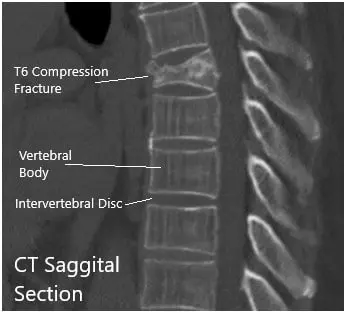

CT revealed moderate acute wedge compression fracture associated with the T6 vertebral body. The posterior cortex of the T6 vertebral body mildly impresses upon the anterior margin of the thoracic dural sac. Minimal hematoma is situated between the T6 vertebral body and the surrounding pleura.

There was a normal configuration of the remaining thoracic vertebral bodies. The thoracic disc spaces are not narrowed. Posterior disc bulges or herniations are not demonstrated. The narrowing is not associated with the thoracic neural foramina.

CT Sagittal and coronal Sections.